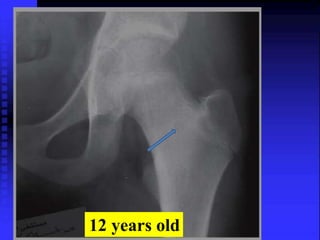

12 years old

Case-6 A 12y old female patient, had hx of chronic pain left knee, limping of 14 m . She used to wake up at night from the pain, she became a well known case to one of the hospital as pethidine addict patient. O/E: mild wasting of thigh muscles, full ROM both lower limbs with no focal tenderness.